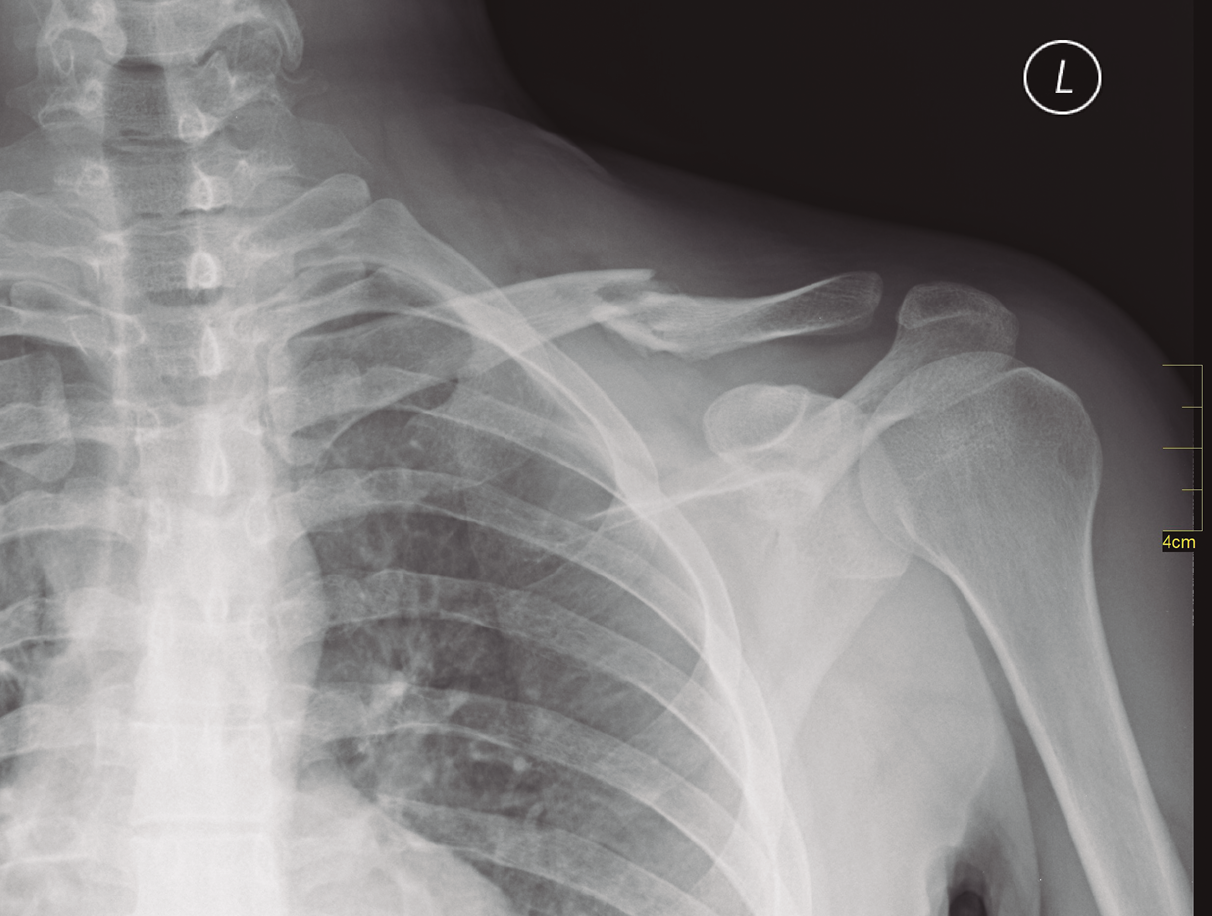

El examen radiológico debe consistir en radiologías simples de la clavícula y el hombro (Figura 2); también es recomendable una tomografía axial computarizada (TAC).

Figura 2. Radiografía simple de una fractura de clavícula en el tercio medio.